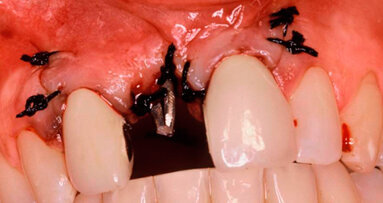

Si programma un intervento di GBR con rigenerazione ossea orizzontale mediante utilizzo di granuli di sostituto osseo eterologo (OsteoBiol Gen-Os) e un device riassorbibile costituito da osso corticale eterologo (OsteoBiol Lamina Soft). A 10 mesi verrà inserito un impianto differito. Dopo aver inciso un lembo mucoperiosteo con incisioni di scarico verticali e scollato sino alla parte più apicale del vestibolo si apprezza l’estrema sottigliezza della cresta residua e la sua corticalizzazione (Figg. 5, 6). Vengono praticati dei fori di 1,4 mm di diametro nella corticale vestibolare per esporre la midollare interna e aumentare la vascolarizzazione del particolato osseo che verrà innestato nel difetto osseo (Fig. 7).

Fig. 5 - Il marcato avvallamento osseo è presente in tutta l’altezza del vestibolo.

Fig. 6 - Visione crestale del difetto osseo.

Fig. 7 - Visione vestibolare del difetto osseo.